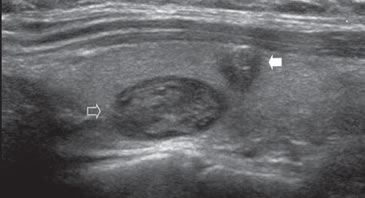

Figura 27. Nódulo coloideo calcificado (flecha) que muestra un

contorno ecogénico anterior y una sombra acústica neta. S: sombra

acústica C: carótida común derecha.

Una o varias calcificaciones centrales también pueden verse en nódulos benignos, y la incidencia parece aumentar con la duración del bocio, pero generalmente no van acompañadas de otros signos de malignidad (Figura 26). Una gruesa calcificación periférica con sombra acústica neta es muy raro que se presente en una neoplasia maligna e indica en la práctica una lesión hiperplástica, que a lo largo del tiempo ha experimentado en forma repetida fenómenos de necrosis, fibrosis y hemorragia (Figura 27). En estos nódulos es prácticamente imposible realizar una PAAF debido a que es muy difícil lograr penetrar en la lesión con la aguja, y generalmente no se obtiene material celular para diagnóstico.